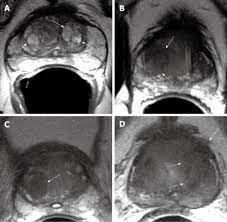

Transitional Zone Prostate Cancer Mri - Multi Parametric Mr Imaging Of Transition Zone Prostate Cancer Imaging Features Detection And Staging / Here are 10 more facts about prostate cancer.

Revisiting Quantitative Multi Parametric Mri Of Benign Prostatic Hyperplasia And Its Differentiation From Transition Zone Cancer Springerlink

Revisiting Quantitative Multi Parametric Mri Of Benign Prostatic Hyperplasia And Its Differentiation From Transition Zone Cancer Springerlink from media.springernature.com